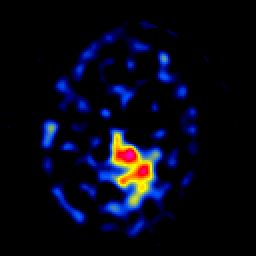

SPECT TL Study #7 -- Slice #38

[Home][Help][Clinical][Tour 1][Tour 2][Tour 3] Slice 38